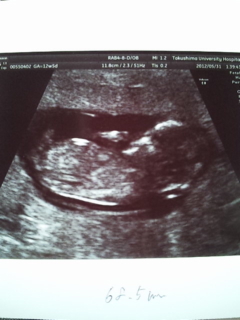

妊娠初期検査と子宮がん検診に行ってきました本当は風邪で病院へかかりたいのに...午前中から夕方まで大きな病院内であっちこっち検査に回りました。まぁ~血液取られたねぇ~軽く献血か!って位に(試験管9本分)色々調べてくれるんですねエコ-は人が変わり3回も診てもらい、チクッとがん検診もやってきました。高齢出産の方は必ず聞かれる「羊水検査」は断りました診察で先生に『風邪でしんどいんですけど...』訴えてみた所『今、1番大事な時なので薬は出せないですが、熱が38.0度になったら軽いの用意します』...やっぱ我慢かぁ 自然治癒に頼るしかないのねずいぶん大きくなりました 頭が右で後ろ向きになってますこれ見ても何が何だか...???の方がほとんどですけど(*´ェ`*)かわゆす(。・_・)ノ”【ポチッと宜しくです】”⇒

何日か前に 淡路島へ行って来ましたぁ用事で行った先がリゾ-ト地 海水浴場でした雲1つ無い空~気持ち良いねでも、鬼瓦がいっぱいで少し怖い...現地の学生さんが作ったものっぽいです。もっと沢山ありましたo(>ロ<o)ヒィ~!!!讃岐うどん...だけど「徳島製麺所」さんへ食べに行きましたやっぱ「釜揚げ」ですね♪ ビックリしたのは「かき揚げ」の大きさ!!! しかも100円!!! 美味しいですいつかのアフタ-はPinky斜め下の「白水」さん...そして食べたのは「素うどん」つわり中は麺類が食べ易いですね~・・・って、つわりの前から麺好きw変わったのは「ラ-メン」⇒「うどん」に変わった所かな?息子と散歩コ-ス「文化の森」で見つけた駐車場でアクビをしていたネコですこのトボけた顔に癒されますwwwそして本日の画像(やっと追い着いた)産婦人科の診察日でした。 10週5日目(妊娠3ヶ月です)母子手帳を貰いに行ったら、22年前の息子の時とは大違いなので色々ビックリでしたウチの可愛い、第二子公開まだ胎児ですけど ちょっとデカいみたいです(笑)10週5日なのに11週2日の大きさだと言う...もっとデカくなるんだろうか?(。・_・)ノ”【ポチッと宜しくです】”⇒